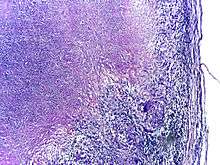

Tuberculosis is classified as one of the granulomatous inflammatory diseases. Macrophages, T lymphocytes, B lymphocytes, and fibroblasts aggregate to form granulomas, with lymphocytes surrounding the infected macrophages. When other macrophages attack the infected macrophage, they fuse together to form a giant multinucleated cell in the alveolar lumen. The granuloma may prevent dissemination of the mycobacteria and provide a local environment for interaction of cells of the immune system.[60] However, more recent evidence suggests that the bacteria use the granulomas to avoid destruction by the host's immune system. Macrophages and dendritic cells in the granulomas are unable to present antigen to lymphocytes; thus the immune response is suppressed.[61] Bacteria inside the granuloma can become dormant, resulting in latent infection. Another feature of the granulomas is the development of abnormal cell death (necrosis) in the center of tubercles. To the naked eye, this has the texture of soft, white cheese and is termed caseous necrosis.[60]